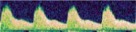

бокового желудочка. При проведении дуплексного допплеровского сканирования выявлено

резко обеднение церебрального сосудистого рисунка (больше - справа), при допплерографии

определялось резкое повышение показателей периферического сопротивления артериального

кровотока в бассейнах передних и средних мозговых артерий с обеих сторон (рис. 3).

|

|

|

| а - нейросонография, В-режим, фронтальная плоскость. Определяется значительное

расширение субдурального пространства справа (белая стрелка), выраженное смещение

срединных структур мозга справа налево, передний рог бокового желудочка справа

компрессирован, слева - дилятирован до 8мм |

б - то же, фрагмент |

в - тот же ребенок, сагиттальная плоскость, фрагмент. Определяется

значительное расширение субдурального пространства справа (белая стрелка), дифференцируется

арахноидальная оболочка (треугольная стрелка) и субарахноидальное пространство

(контурная треугольная стрелка) |

г - тот же ребенок, сагиттальная плоскость, дуплексное допплеровское

сканирование. Зна-чительное обеднение церебрального сосудистого рисунка, Расширение

субдурального пространства (белая стрелка) |

д - тот же ребенок, допплерография на средней мозговой артерии справа. Резкое

повышение показателей периферического сопротивления (RI = 1,0) с исчезновением

диастолического артериального компонента |